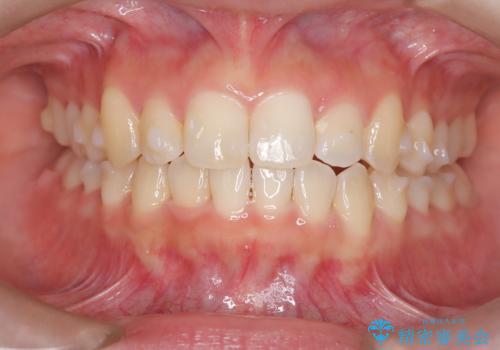

前歯の逆の咬み合わせを、目立たない矯正でスムーズに改善

- 右上の前歯(2番)が下の歯より内側に入っている反対咬合を主訴にご来院されました。精密な検査の結果、この反対咬合を解消するためには、右上の歯列に前歯を出すためのスペースを確保する必要があると判明しました。患者様のご希望に合わせ、透明で目立たないインビザライン(マウスピース矯正)による治療計画を立案。奥歯全体を奥へ動かす遠心移動でスペースを作り、反対咬合を解消することを目指します。

今回の矯正治療では、透明なマウスピース型の装置インビザラインを使用しました。治療は、緻密なデジタル計画に基づき、奥歯から順に歯列全体を後方へ移動させる遠心移動を実施し、前歯を前に出すためのスペースを確保しました。このスペースを利用して、内側に入り込んでいた右上2番をスムーズに前方に誘導し、正常な咬み合わせへと改善。目立たないインビザラインで、機能的な咬み合わせと美しい前歯の並びを獲得していただけました。